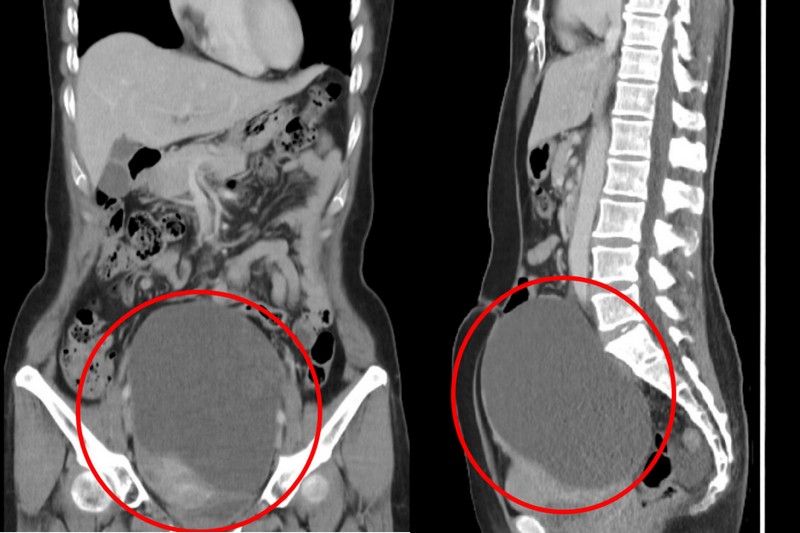

家芸最初發現腹部越來越大,原本以為是中年後代謝變差導致的肥胖,直到按壓會感到輕微不適,才輾轉家醫科、腸胃科就診,最後竟在婦科確診卵巢癌第一期;電腦斷層影像顯示,一個16公分大的卵巢腫瘤佔據了她的卵巢所有空間,其中包含實體瘤及一塊疑似惡性腫瘤的陰影。

右圖;電腦斷層顯示家芸的腹部內有一顆16公分的巨大卵巢腫瘤。